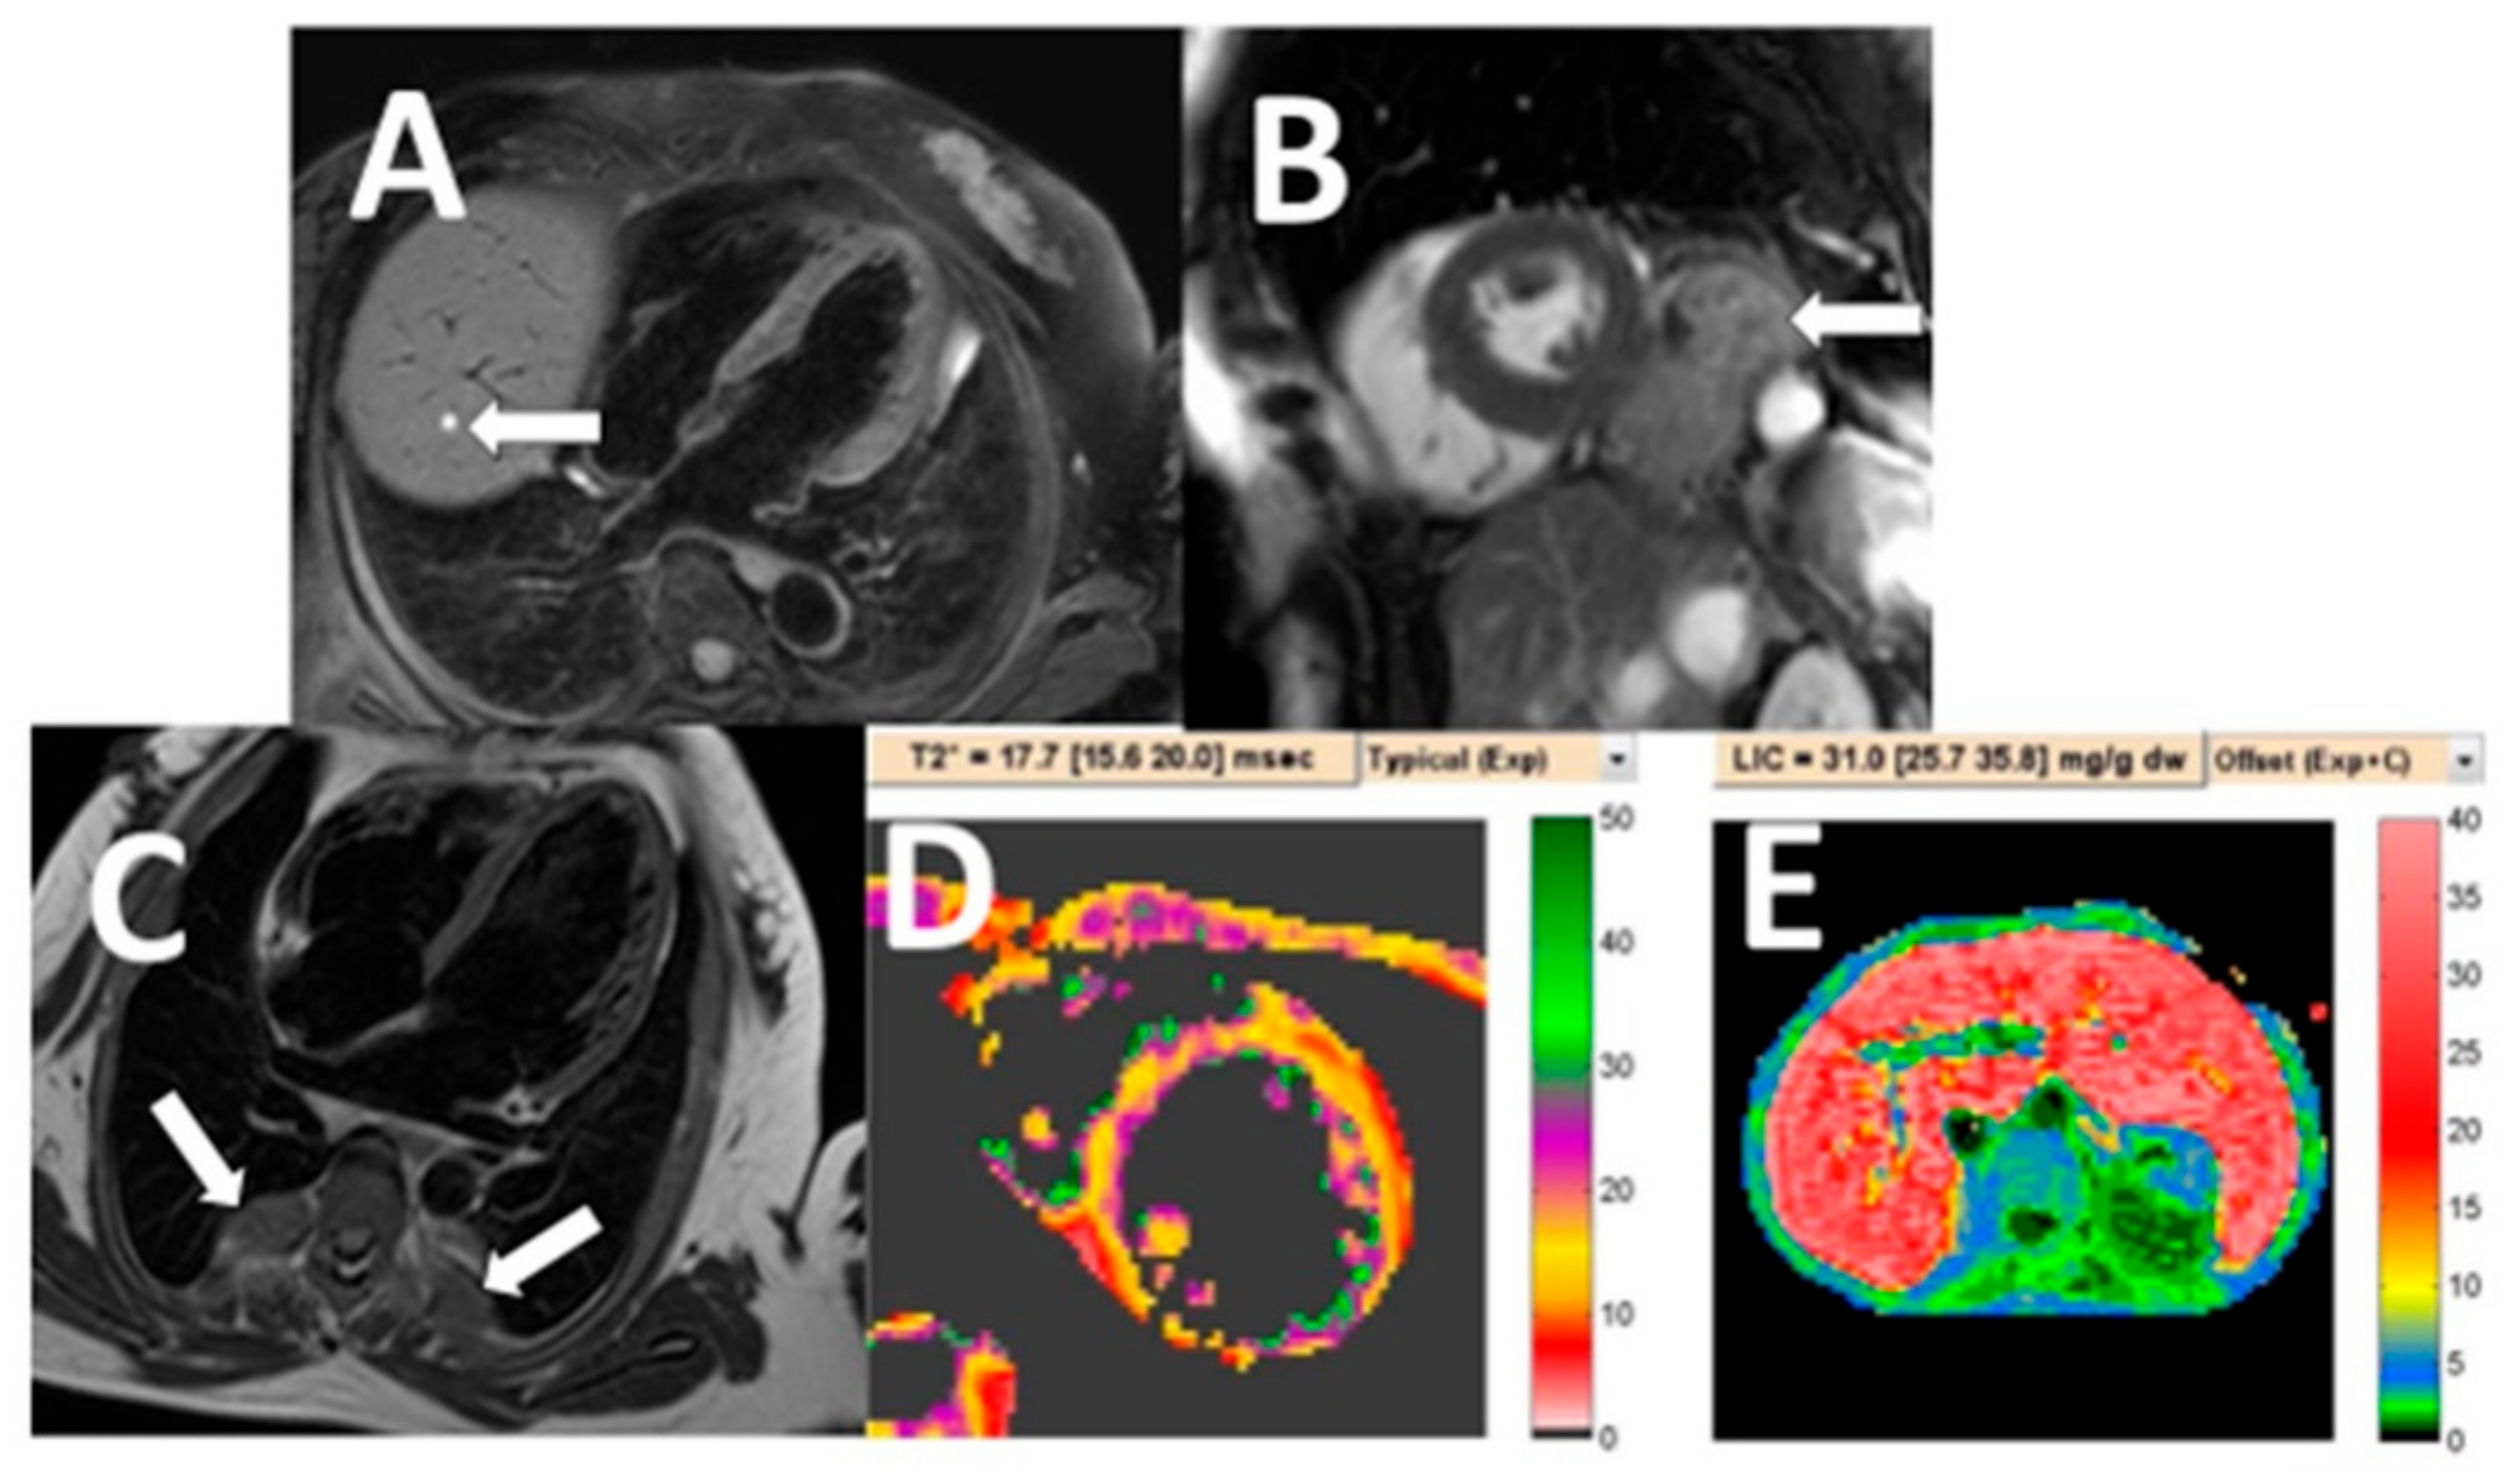

3. Results